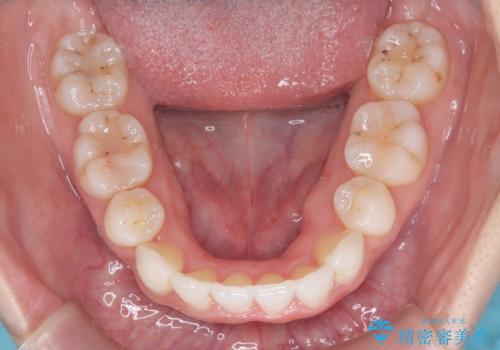

【抜歯インビザ】凸凹を綺麗になおしたい

- 前歯の凸凹を主訴に来院されました。

叢生量が多いため、抜歯が必要となるため、ワイヤー矯正をお勧めしましたが、患者さんの希望によりインビザラインで治療を開始しました。途中でワイヤーリカバリーを必要とせず終了でき患者さんには満足していただけました。